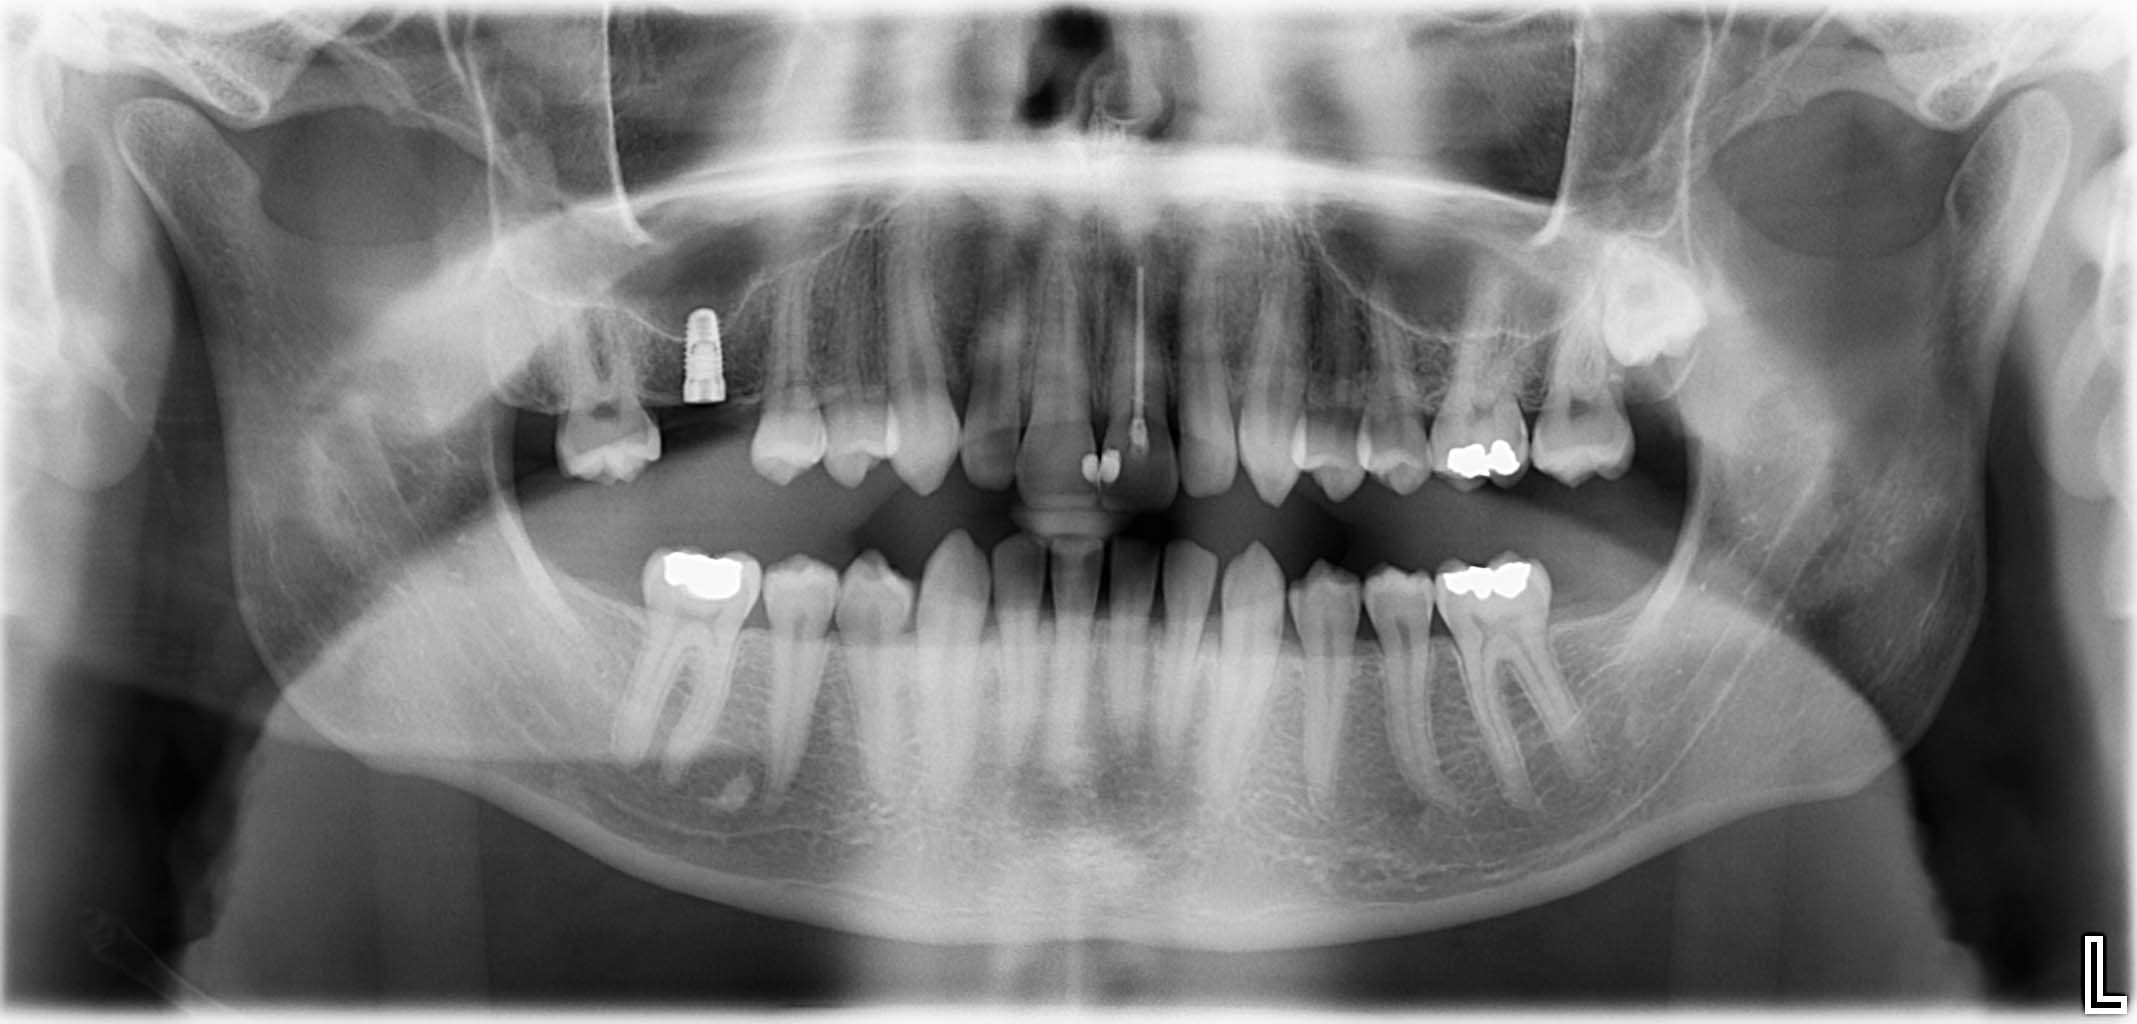

Erfolgreich implantierte Patientenfälle (klinische Fotos)